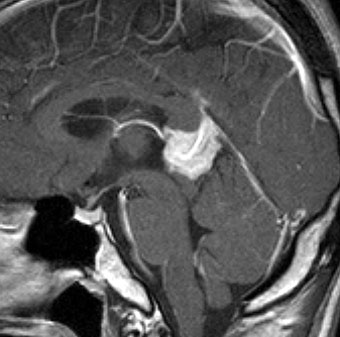

10歳くらいから身長の伸びが遅くなって,12歳で食欲低下と体重減少がありました。左のMRIはガドリニウム造影MRIで,視床下部と下垂体を侵す神経下垂体ジャーミノーマです。CTでは小さな石灰化(白い点)がみえます。CT検査は不必要なものでした。

尿崩症にて発症した2年後にようやく小さなneurohypophyseal germinomaを発見された9歳女児例です。術前のT1強調画像では下垂体後葉のbrightnessが消失し,下垂体柄が腫大しています(左側)。ガドリニウムで腫瘍部分が増強されますが前葉よりは低信号となっています(右側)。経蝶形骨洞生検術で確定診断を得た後に,シスプラチンとエトポシドを1コース投与したところ腫瘍は完全消失しました。3コース後に24Gy12分割の放射線治療を加え再発はありません。残っていた下垂体前葉機能は治療後に少し改善しました。生検術では,トルコ鞍底を開けて下垂体後葉の下部を目標にして小さな組織採取をします。GHDがあっても前葉にはmassとしての腫瘍が無いと考えた方がいいでしょう。

血清HCGが2.1mIU/ml,尿崩症で発症した思春期男児です。石灰化はありませんし,脂肪組織なども混在しません。生検術をしなくてもgerminomaと診断できます。でも簡単なので,経鼻的な生検術を行った方がいいです。

この例は18歳,HCG 0.1mIU/ml,尿崩症で発症しました。神経下垂体ジャーミノーマなので,下垂体前葉のみが残って後葉から視床下部が腫瘍化しています。よくよく見ると松果体にもごく小さな腫瘍があります。右のCISS画像で松果体の腫瘍化が明瞭です。